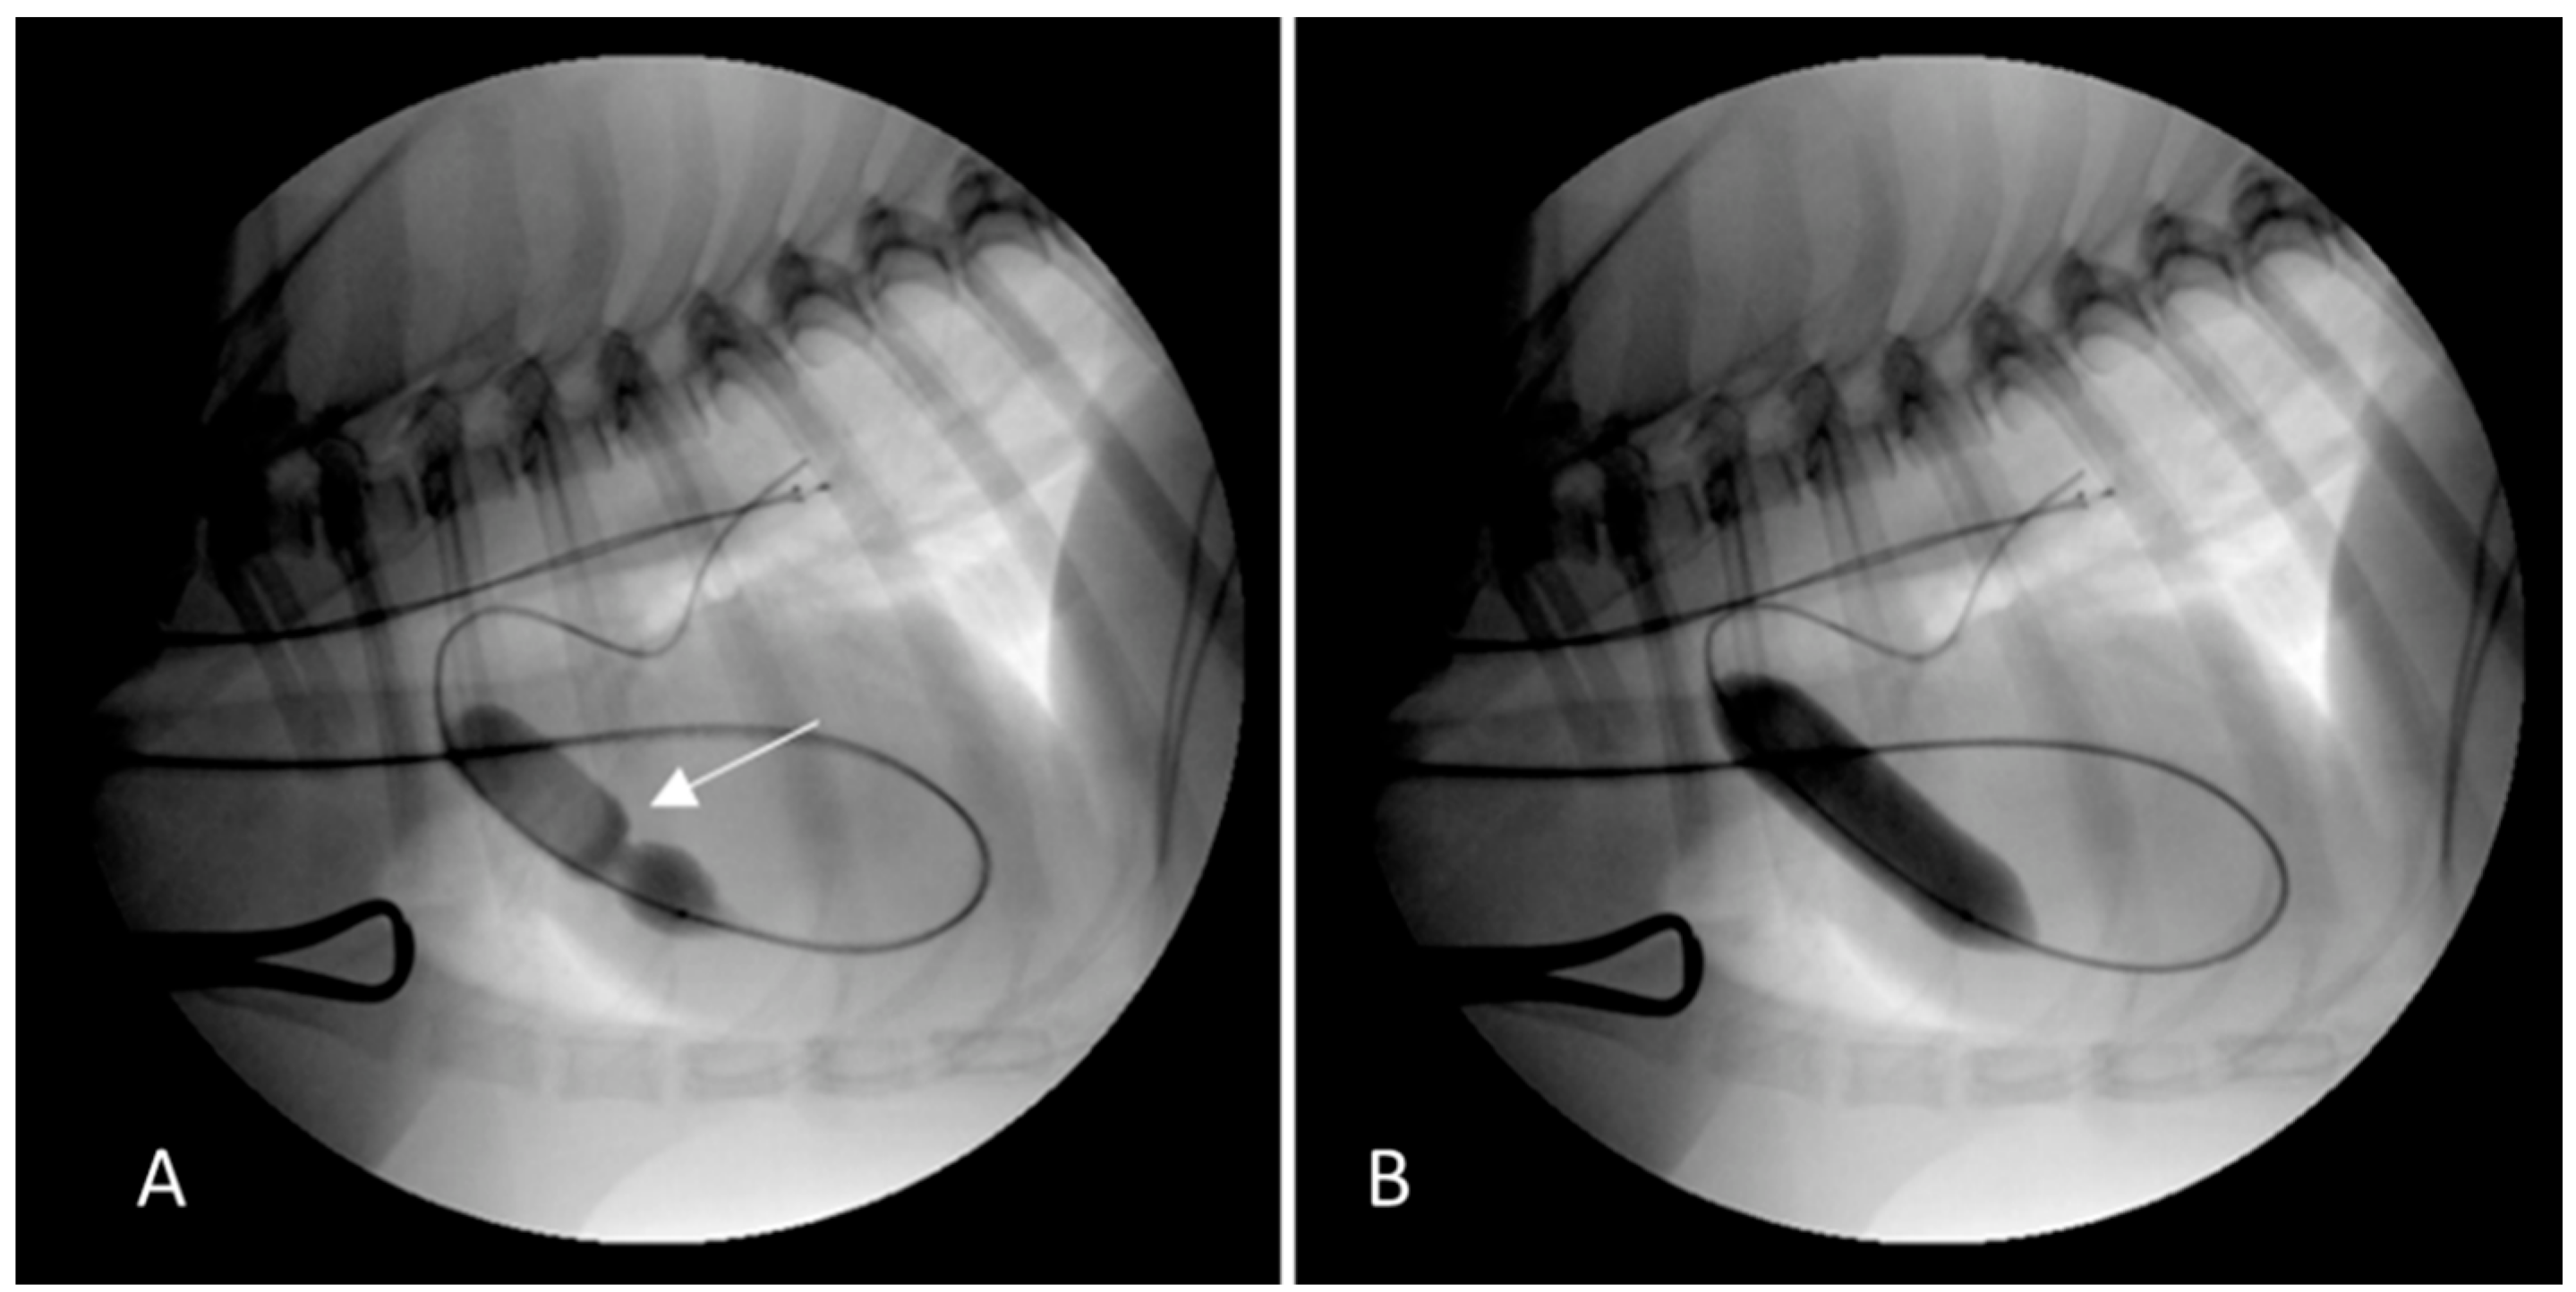

2.1. Case 1